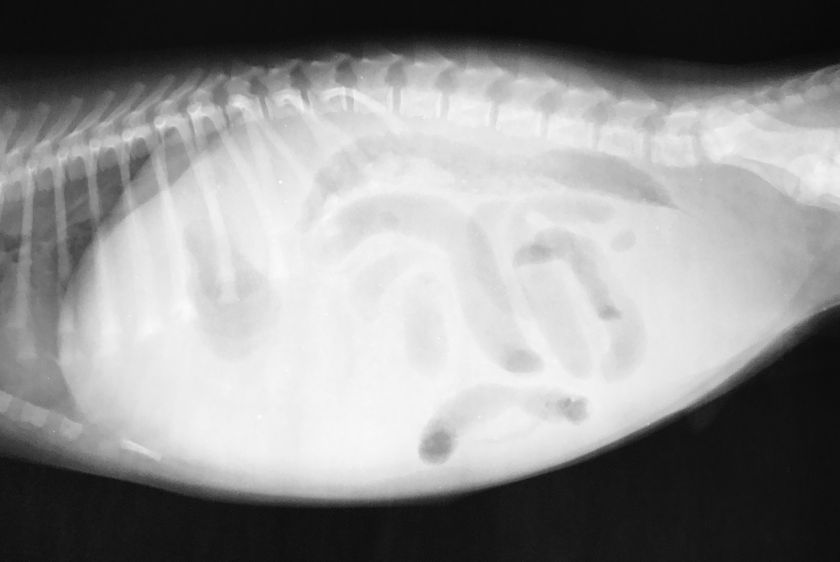

- Une échographie et/ou une radiographie de la cavité abdominale. Ces examens permettent de déterminer la taille des organes internes, ainsi que la présence ou l'absence de tumeurs.